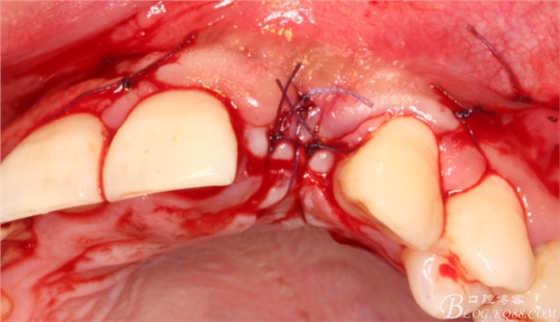

有老師問我,為什么不在此時(shí)同期植骨同期植入植體?我的觀點(diǎn)是:不要一次做太多事情,做得越多風(fēng)險(xiǎn)越高。再說,此時(shí)軟組織不健康,沒有健康的軟組織如何能保證GBR的成功?所以,我僅放了一塊膠原蛋白就縫上了。

事實(shí)證明,我的做法沒有錯(cuò)誤,一個(gè)月后,軟組織健康愈合。鄰牙軟組織沒有退縮。